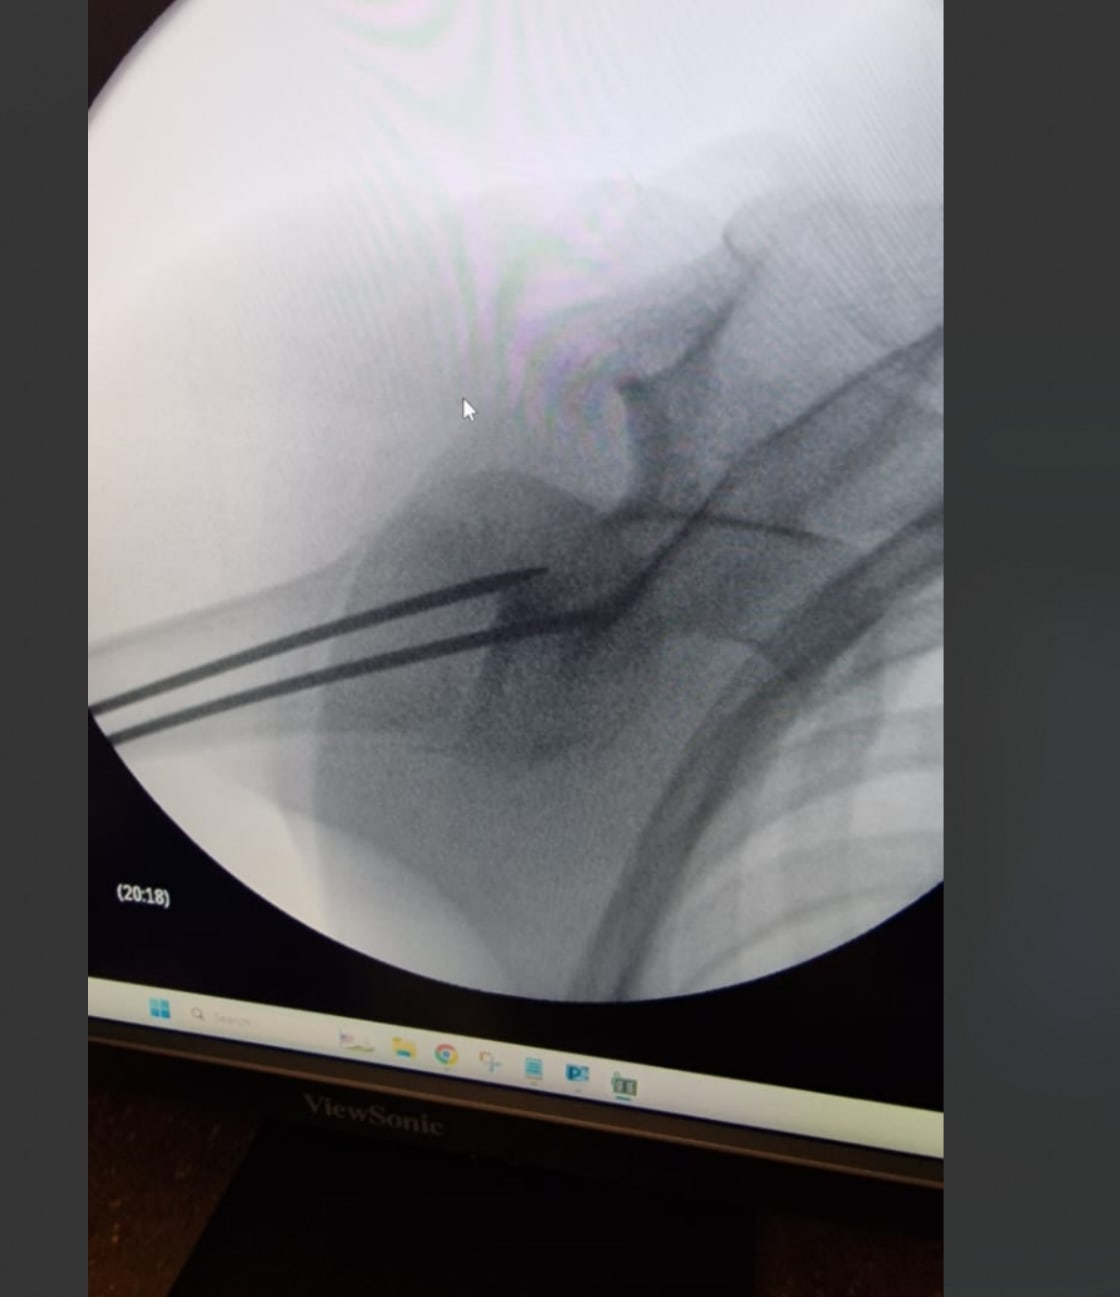

Comme cela a un peu causé du système américain, petit rapport d'il y a 48 heures. Mon gamin se fracture l'humerus en snowboard. Je l'emmène vers 14H à l'hosto après qu'il ait été pris en charge gratos par la station pour les premiers soins, me conseillant d'aller faire une radio, on ne sait jamais car il souffre un peu.

Présentation du passeport et direct en salle d'urgence. Cela m'a rappelé les épisodes du docteur House, plusieurs infirmières ou aides soigantes se succèdent, chacune avec un rôle précis, gestion de la douleur et prescription, observation des symptômes, puis manip radio qui l'emmène 5 mn. Tout ceci prend 1H. Après 10 mn, une autre infirmière revient m'informant que l'humerus est fracturé, qu'ils viennent d'appeler le chir qui décidera quoi faire. Il arrive 30mn après avec la radio me dit qu'il va l'opérer dès qu'un bloc se libère. La douleur monte chez le gaminqui pleure, et hop, oxycodone, redoutable d'efficacité en 5mn. Il est 17H,; le chir revient me disant que un bloc s'est libéré, et nouveau balai avec d'autres infirmières puis l'anesthésiste et le chir qui me détaille l'intervention. Bref, ils me le rendent à 18H30 en salle de reveil et à 20H30 on était rentrés.

Hopital nickel, matos de dingue et petit hopital de station de ski dans une ville de 20 000 habitants je pense.

Incision de 2.5 cm pour remettre en place la tête d'humerus fracturée et déplacée, suture nickel. chapeau.